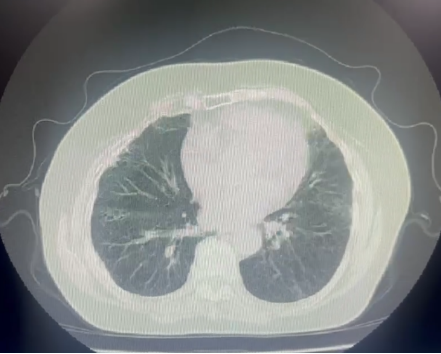

CT 影像:11 月 27 日复查胸部 CT,可见双肺磨玻璃渗出影明显吸收,对比 11 月 18 日影像,肺部病变改善显著。

11月27日肺CT:

11月27日肺部CT